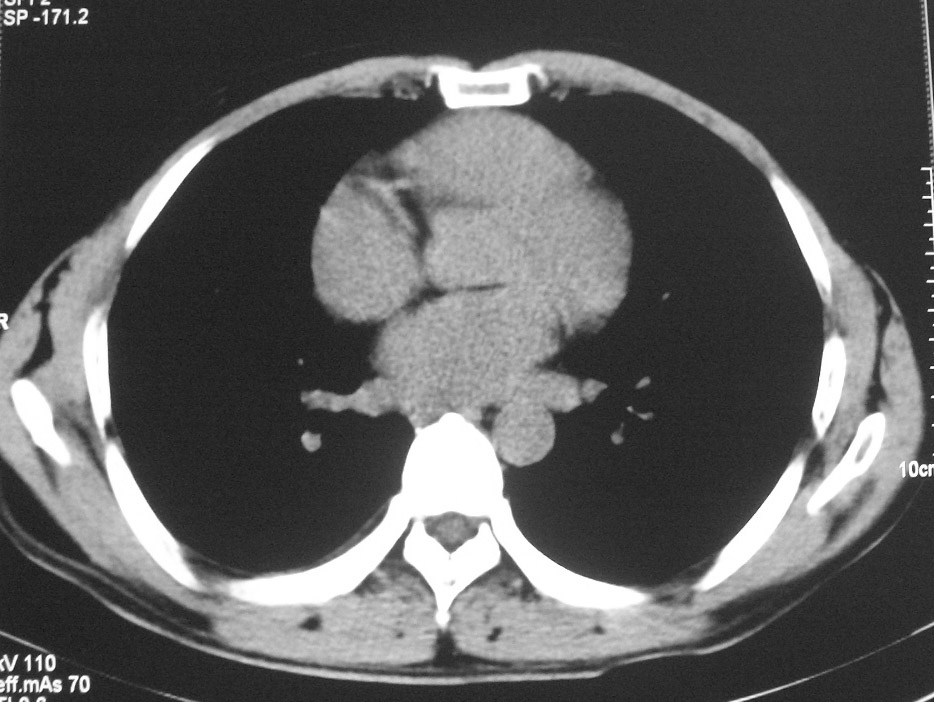

标题: CT5485:[原创]肺部占位请讨论

右肺上叶中央型肺癌并上叶肺不张、纵隔淋巴结肿大

右上叶支气管肺癌并右上叶阻塞性不张,右侧少量胸腔积液.

右肺上叶中央型肺癌并上叶肺不张、纵隔淋巴结肿大.右侧少量胸腔积液。

右上肺中心型肺癌并肺不张,纵膈淋巴结肿大。右侧少量胸腔积液。

右肺上叶不张,考虑中央型肺癌。右侧胸膜肥厚

右肺上叶中央型肺癌并阻塞性炎症、阻塞性肺不张……

右上肺癌,肺不张,纵隔淋巴结肿大